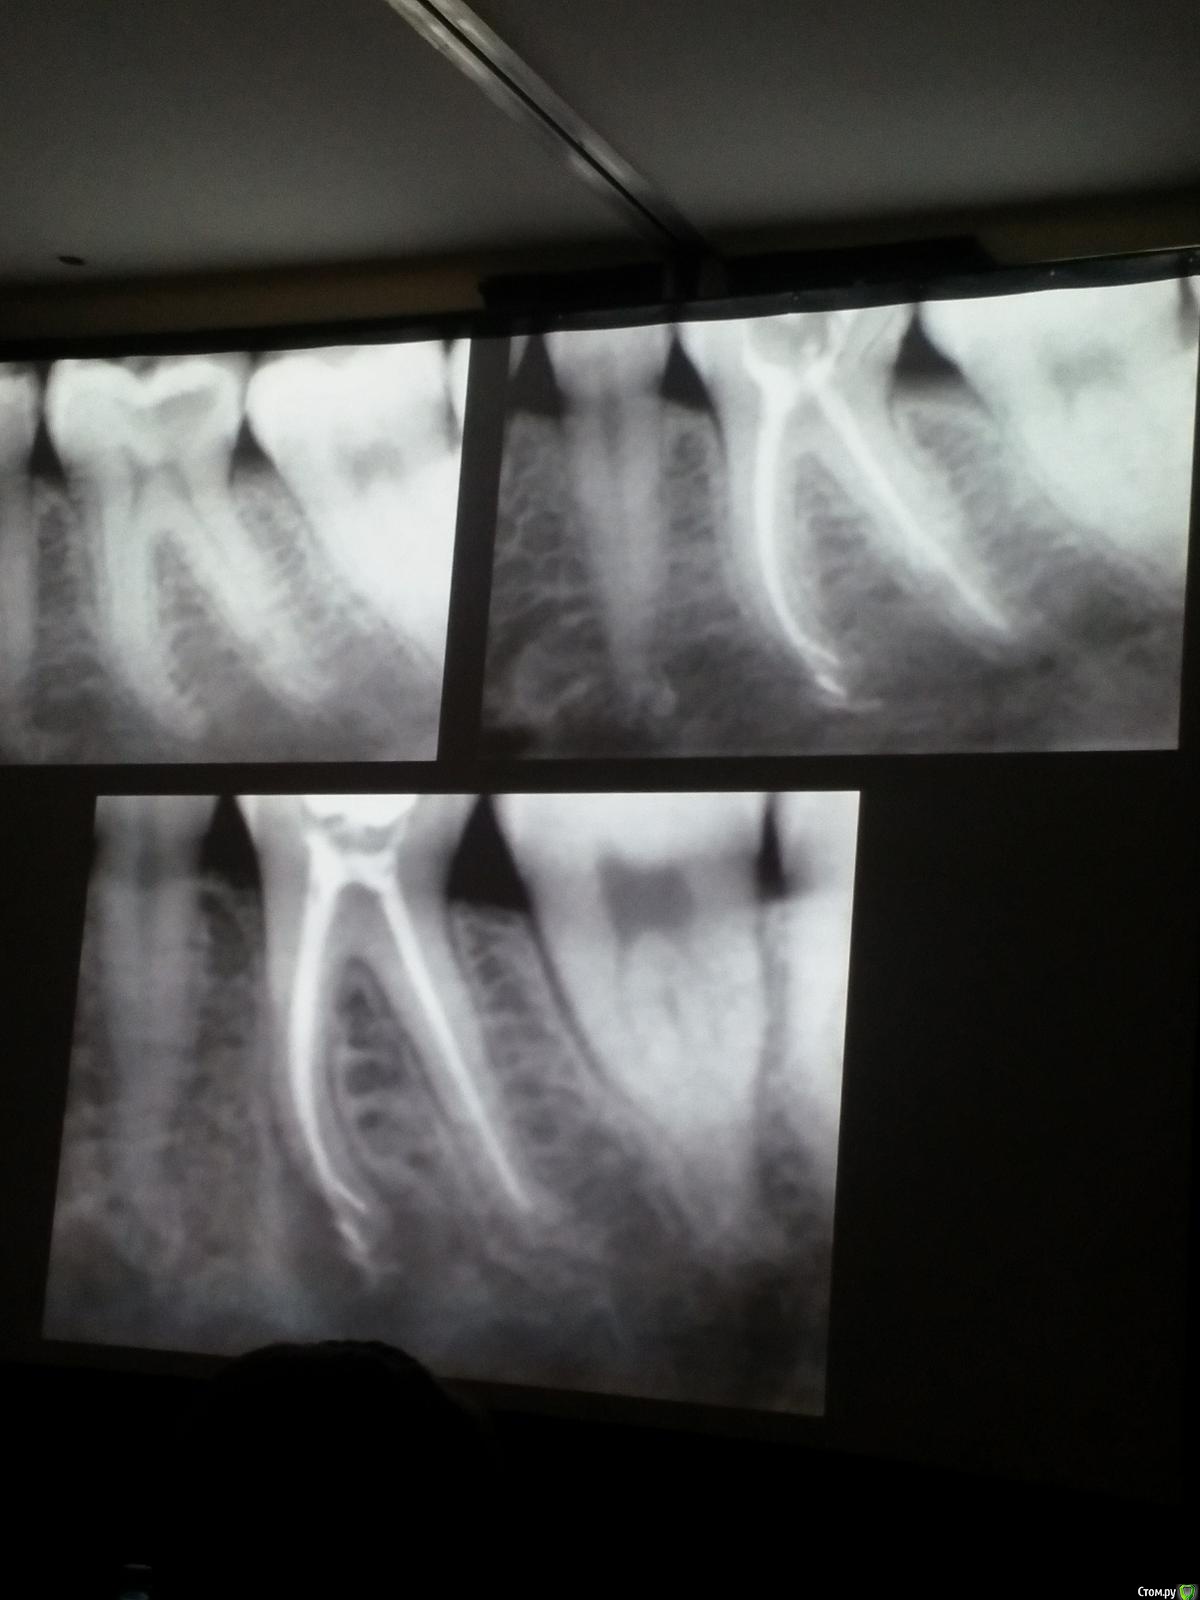

Популярный пост Kolchanov Опубликовано 11 марта, 2017 Популярный пост Поделиться Опубликовано 11 марта, 2017 (изменено) Товарищи, скажу я вам...........Вкратце. Может я где-то что-то и приврал, надеюсь, кто еще был, поправят. Честно говоря немного прибалдел от уровня Доктора. Очень, очень высоко! Приедет еще раз, пойду еще. 1) Фиссуры зондирует острым зондом и выпиливает все дотла. По факту у него уже пломбы, а не герметизация.2) Bite-wing у первичных пациентов всегда.3) Если кариес диагносцирован, то лечить его, пофиг какой он там. Эмали, дентина…4) Препарирует до твердого (или до вскрытия J ). CAD, СID… в топку. Кариес маркером не пользуется, проверяет острым зондом/экскаватором. Вычищает все дотла. Считает, что даже небольшое количество бактерий в дентине под пломбой вызывают хроническое воспаление в пульпе. С его слов у него на контроле где-то 500 вскрытий, не удивительно при таком подходе к очистке.5) Тщательная изоляция. Коффер порвался – меняет. Большое значение герметичности реставрации. под замену6) Критерии обратимости и необратимости.Гистологически, обратимый тот, что без абсцессов в пульпе, но клинически это понять нельзя, только предположить.Здесь был бы обратимый, если бы не удалил. Нет микробов в пульпе. Линия - граница обработки.Покрытие 27 лет назад. Dycal, СИЦ, композит. От дайкала одно воспоминание.7) Вскрылись. Размер перфорации, возраст и прочее не играют роли, важно только состояние пульпы, т.е. диагноз.Примеры перфораций.8) Кровотечение останавливает стерильным ватным шариком. Если останавливается, то покрытие, если нет, то пульпотомия или пульпэктомия.9) Использует гидроокись кальция (порошок), перекрывает Dycal или СИЦ. Потом восстановление Нередко под IRM, потом все убирает (через пару-тройку месяцев) и смотрит, что получилось. Порой приходится повторять! Использует и МТА, его тоже убирает.10) Наблюдение 6мес, 1 год, 2…. Все может провалиться и через месяц и через 24 года.Примеры проваловНиже - 24 года спустя появилась дуля. 11) Неравномерная облитерация полости зуба на RG (после покрытия) – признак текущего хронического воспаления, где-то остались микробы. Рекомендует эндо.12) Мостик который образуется – это не дентин! И одонтобласты не регенерируют и новые не образуются. Что это такое он и сам не знает, но раз это твердые ткани, то и наплевать.Вот фиолетовое это дентинные опилки вмурованные в розовую ткань бог знает кем сформированную.13) Пульпотомия в зубах с несформированной верхушкой и в сформированных, при подозрении на частичное поражение коронковой пульпы. Иссекается стерильным алмазным бором часть пульпы, гидроокись, временная пломба на 90 дней, после повторное раскрытие, оценка результата, восстановление в случае формирования твердых тканей. Гипохлоритом можно мыть, можно не мыть, если мыть, то 0,5-1%.14) В апикальной части пульпа чаще витальна, чем нет.15) Периапикальные поражения возникают по причине поступления токсинов микробов с током крови, а не самих бактерий.16) За апикальные расширения в полностью некротических случаях. Надо механически отодрать биопленку и срезать инфицированный дентин. На ирриганты надежды мало.17) Биопленка на поверхности в 6% случаев.Синенькие пид@расы18) Обработку проводить нежно, краун-даун. Чередовать с H-файлом, чтобы посмотреть докуда распространяется некроз.19) Патенси в витальных кейсах не колоть, сохранять витальную пульпу в констрикции!Формирование еще большего сужения в констрикции за счет сохранения витальной пульпы. Изменено 11 марта, 2017 пользователем Kolchanov 31 Ссылка на комментарий

Популярный пост Kolchanov Опубликовано 12 марта, 2017 Автор Популярный пост Поделиться Опубликовано 12 марта, 2017 Второй день.1) Дезинфекция зуба и раббер дама перед работой. Вначале установка системы, потом протирка тампоном 30% перекиси, потом протирка всего йодинолом. Потом преп, потом повторение и только потом доступ к к/к. Все старые реставрации надо убрать, кариес убрать, противник лечения через коронку.2) Гидроокись на неделю. Замешивает на стерильном физрастворе. При необходимости повторяет. Т.е. в случае сохранения свища, симптоматики, экссудации, запаха. Если свищ не исчезает после трех смен временных вложений, то хирургия.3) Пломбирует латеральной компакцией. Лучше контроль длины обтурации.4) Высушивание канала стерильными штифтами, на рабочую длину минус 1мм. После высушивания штифт оставляется на 60с. в канале и должен выйти сухим.5) Определение рабочей длины. Витальные случаи. АЛ должен три раза дать одну и ту же картинку в определенной точке + проверка RG. Девитальные случаи. На АЛ полагаться сложно, т.к. из-за наличия резорбции констрикции может врать, больше ориентируется на RG.6) Использует ЦОЭ силеры. Резорбируются при незначительном выведении. Резорбируются в канале, позволяя закрыть апекс цементоподобной тканью. Вот так вот.Случаи исчезновения силера, как за пределами канала так и в канале7) Выведение материала (не важно какого) в большом объеме способно вызвать защитную реакцию тканей. Которая должна пройти спустя некоторое время. (иногда это будет 25 лет J Случай 1ый. Студенты наломали инструментов. Периодонтит на RG через год. Резекция и гистология. Бактерий не обнаружил. Да, маленькое замечание. Каждый препарат дает 500-600 срезов. И ищет он на всех. Объем работы, конечно….Случай 2й. Его собственный. Периапикальное поражение, обнаруженное на реколле через 10 лет зажило еще через 15.8) «Функционирующий зуб» считает результатом неприемлемым. Осталась инфекция с которой надо что-то делать. То, что бактерий можно замуровать в дентинных трубочках и под пломбировочным материалом, считает неправильным. Продукты метаболизма один фиг будут просачиваться и могут поддерживать реакцию воспалительную.Случай. Синее – маленькая кучка микробов, предположительно, препятствовавших заживлению очага.9) Биопленка на поверхности корня может принимать вид кальцификатов (камней) и тут уже только хирургия в помощь. При длительном существовании свищевого хода, например.Черное - это камни вокруг апикального отверстия. И гистология их с кучей синих микробов.Здесь камни на фуркации и отсутствие заживления и свищ даже после ретроградной обработки и пломбировки.А здесь вообще чертова уйма камней. И зацените разветвление канала в этом боковом резце (последнее фото препарата). 10) Реваскуляризация.В некротических случаях дентина не образуется, т.к. одонтобластов нет и не будет новых. Образуется та самая бог знает какая ткань, которая даже и с корнем не связана может быть. Суть здоровый дентикль-петрификат. А в витальных это не реваскуляризация, а обычное формирование корня. Так что нечего тут.11) Трещины дентина.Советует расшивать, братья и сестры. Без фанатизма, если нет симптоматики, но, по возможности максимально. Если есть симптоматика, то там уже по обстоятельствам. Чертова уйма микробов там и ползет, ползет к пульпе. Надеюсь, что еще раз этот замечательный Доктор приедет. Схожу с удовольствием. 2 23 Ссылка на комментарий